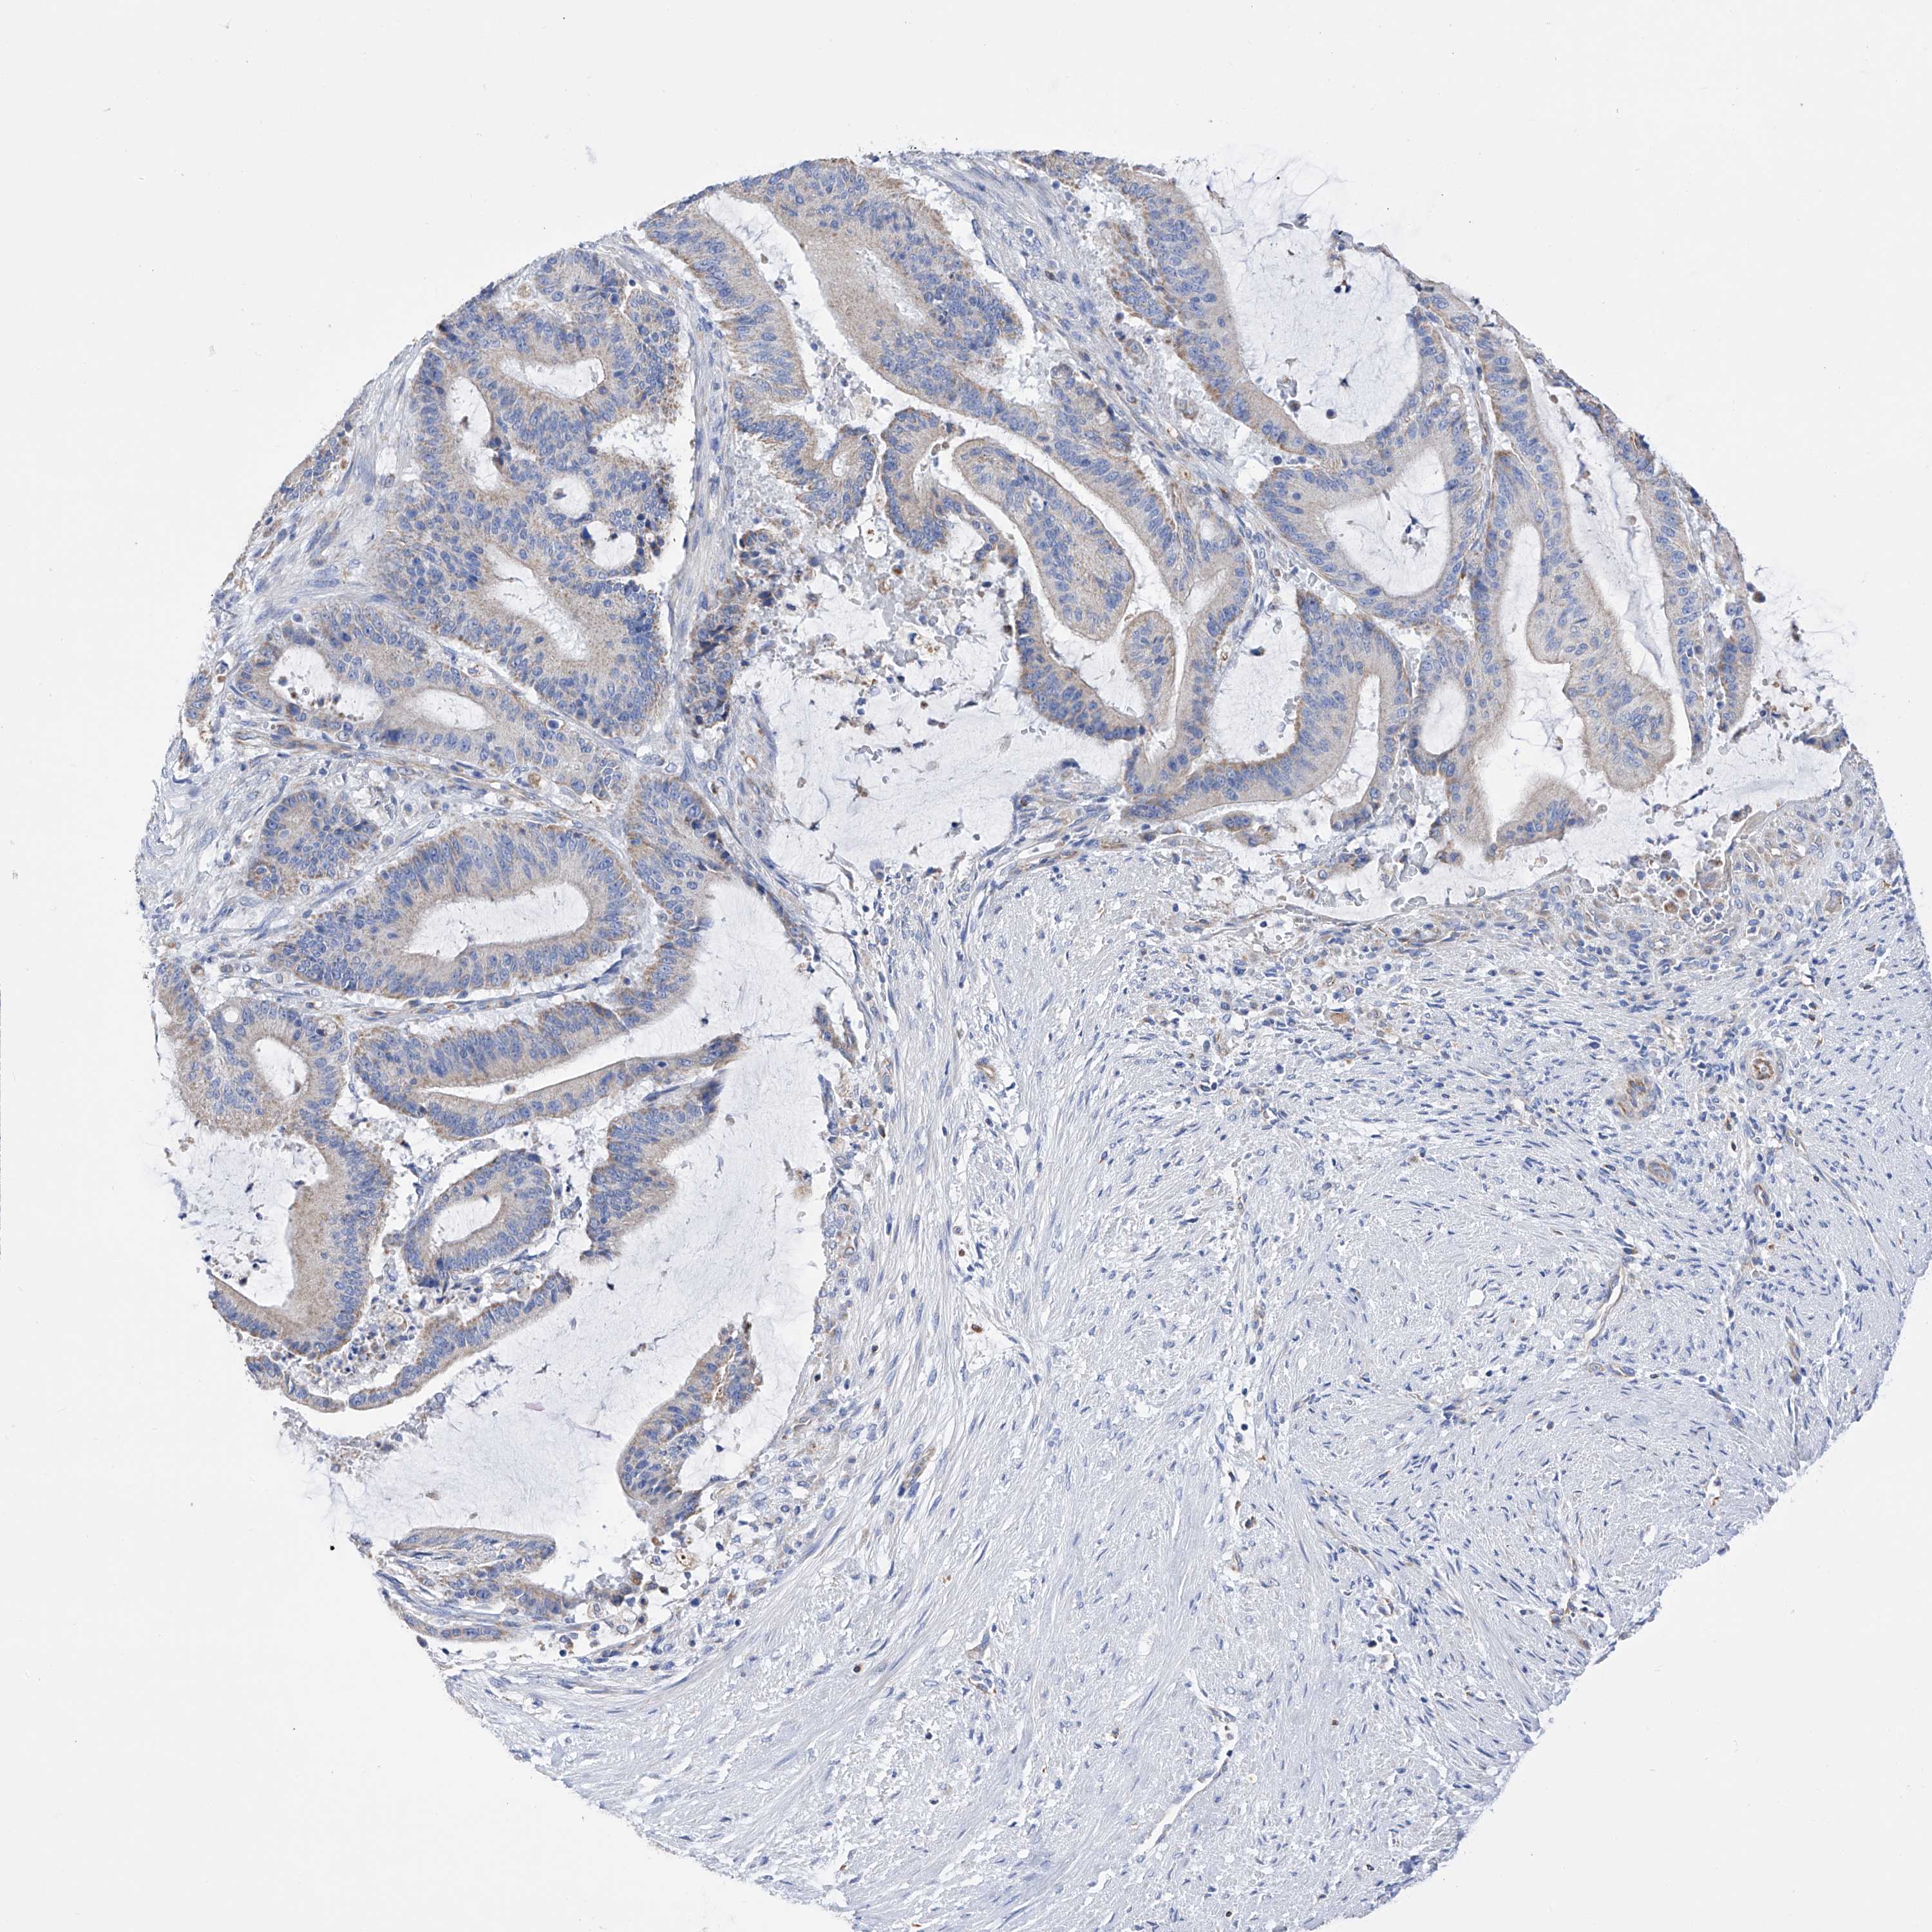

LIVER CANCER - Protein expressioni

A mouse-over function shows sample information and annotation data. Click on an image to view it in a full screen mode. Samples can be filtered based on level of antibody staining by selecting one or several of the following categories: high, medium, low and not detected. The assay and annotation is described here.

Note that samples used for immunohistochemistry by the Human Protein Atlas do not correspond to samples in the TCGA dataset.

Antibody stainingi

Antibody staining in the annotated cell types in the current human tissue is reported as not detected, low, medium, or high, based on conventional immunohistochemistry profiling in selected tissues. This score is based on the combination of the staining intensity and fraction of stained cells.

Each image is clickable and will lead to virtual microscopy that enables deeper exploration of all samples and also displays staining intensity scores, fraction scores and subcellular localization as well as patient and tissue information for each sample.

Antibody HPA030188

Antibody HPA030189

Antibody CAB002210

Staining

High

Medium

Low

Not detected

Intensity

Strong

Moderate

Weak

Negative

Quantity

>75%

75%-25%

<25%

None

Location

Nuclear

Cytoplasmic/membranous

Cytoplasmic/membranous,nuclear

Cholangiocarcinoma

Carcinoma, Hepatocellular, NOS